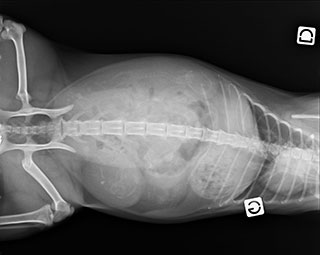

2015-09-12 : 3 ? 4? encore un peu d’incertitude…. 🙂

2015-09-26 : Ils sont nés et ils sont 4 ! :3